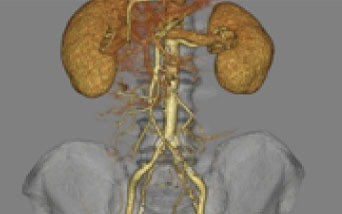

大動脈CT

造影剤を用いて撮影することにより、大動脈瘤、解離性大動脈瘤、血管の閉塞、狭窄の検出に優れています。

VR表示